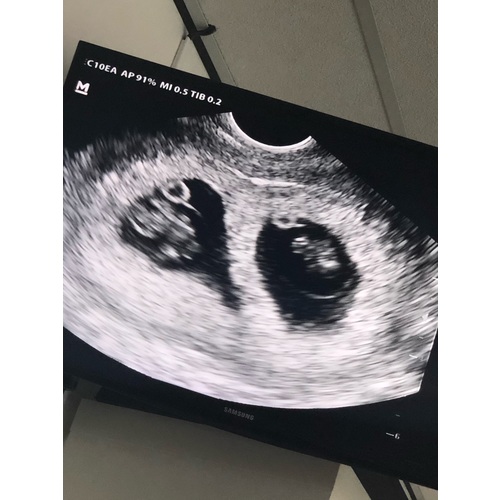

Gefeliciteerd!!!! Wat leuk!! Zie ik het goed dat het twee vruchtzakjes zijn ...

Dankjewel, ja dat klopt hihi!